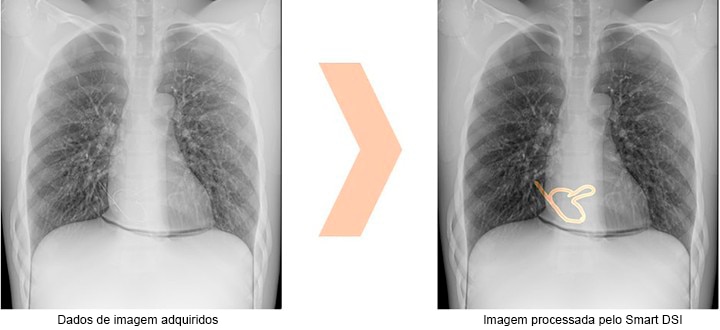

Suporte para Confirmação de Objetos Cirúrgico Retidos – Processamento de Imagem (Opcional)

O Smart DSI auxilia na identificação de objetos cirúrgicos retidos no corpo, realçando áreas da imagem que podem indicar a presença de agulhas cirúrgicas, gazes ou outros corpos estranhos.

No vídeo a aplicação do Smart DSI é demonstrada

*Não confie apenas nas capacidades de processamento de imagem do Smart DSI para determinar a presença de objetos estranhos. É essencial realizar também a confirmação visual da imagem, a contagem de gazes e utilizar outros métodos de verificação.